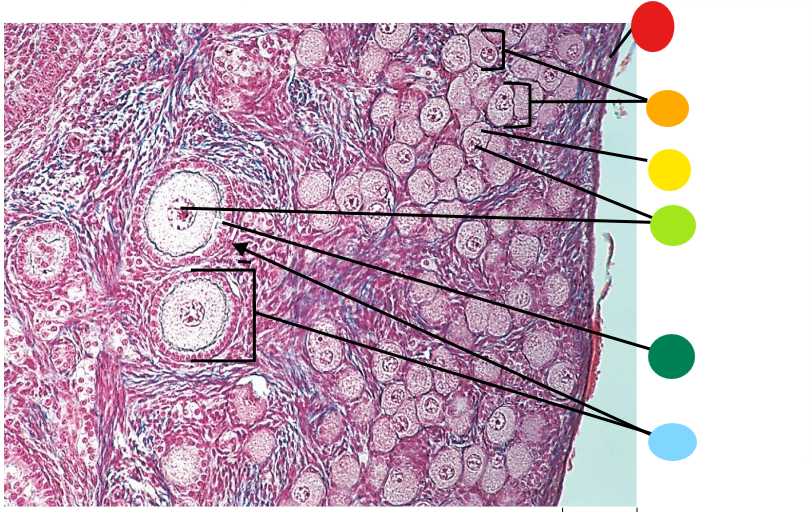

red

primary oocyte

orange

zona pellucida

yellow

granulosa cells

light green

developing thecal cells

What is this

secondary follicle